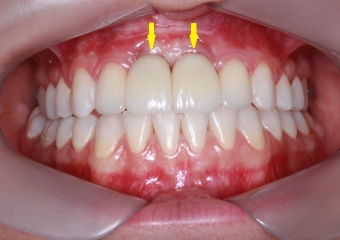

Imagem Inicial 2014

Imagem após enxerto ósseo